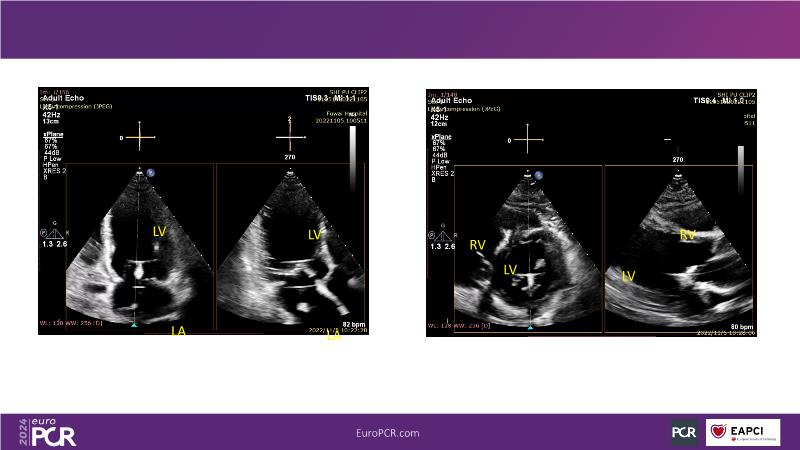

Watch this session to gain insights into the clinical evidence of mitral TEER therapy for the Asian population, learn techniques for implanting a MitraClip in patients with challenging anatomy, and understand how to use the four clip sizes for optimal outcomes. The session also covers educational aspects of clipping in dextrocardia, the benefits of reserve bending of the transseptal needle for tenting and puncture, new steering maneuvers for dextrocardia patients, and the importance of understanding anatomy and collaborating closely with the echo team for success.